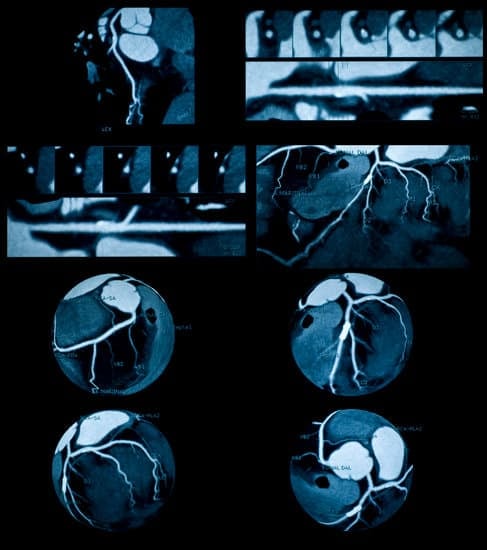

위조영술(Barium Swallow)은 위장관의 구조와 기능을 확인하기 위해 **조영제(바륨)**를 복용한 뒤X선 촬영을 통해 식도, 위, 십이지장의 이상 유무를 확인하는 검사입니다.

바륨은 X선에 잘 보이는 물질로, 이를 통해 장기의 모양, 운동, 병변 여부를 자세히 파악할 수 있습니다.

X선 촬영:

검사자는 서 있거나 누운 자세로 여러 각도에서 실시간으로 위장관 움직임을 관찰합니다.

촬영 중 자세를 바꾸며 위장관 전체를 정밀하게 촬영합니다.